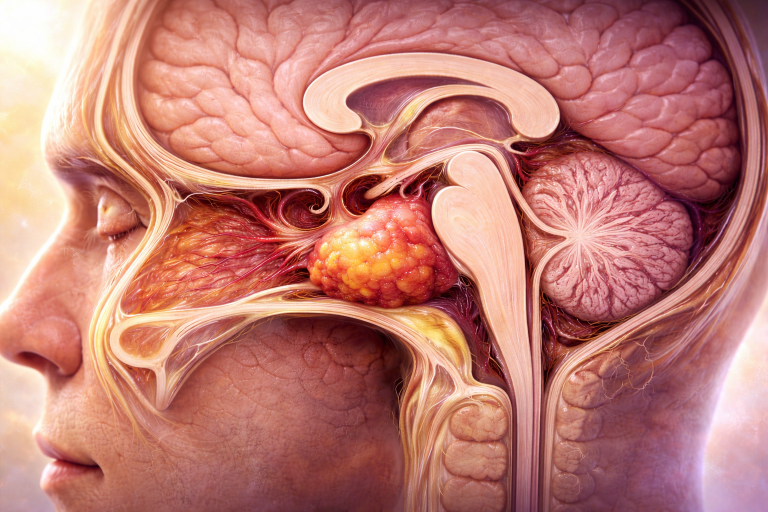

Craniofaringioamele reprezintă tumori benigne cu origine embrionară, care apar în regiunea selară și supraselară a creierului, în apropierea hipofizei și hipotalamusului. Deși sunt tumori benigne din punct de vedere histologic, comportamentul lor clinic poate fi agresiv, din cauza localizării sensibile și dificultății de rezecție chirurgicală completă.

Localizare și creștere tumorală

Craniofaringioamele au localizare predominant supraselară, dar pot avea extensii variabile în zona selară, hipotalamică, chiasmatică și ventriculară. Frecvent, tumora comprimă structurile din vecinătate, inclusiv hipotalamusul, hipofiza, chiasma optică, arterele cerebrale anterioare și ventriculii laterali. Această poziționare explică simptomatologia complexă, care poate include tulburări endocrine, neurologice și vizuale.